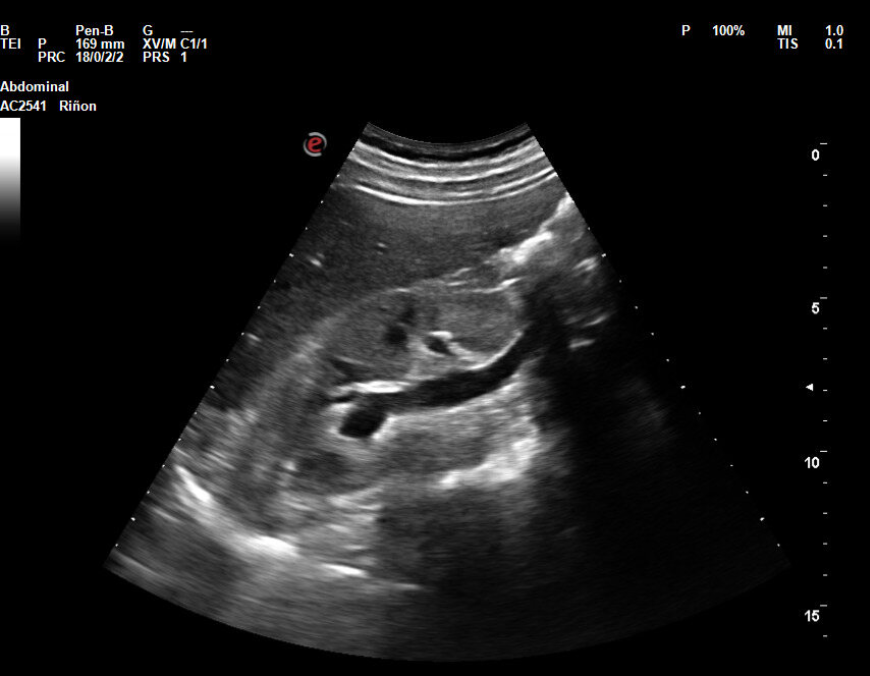

Hallazgos ecográficos

En la ecografía objetivamos discreta dilatación calicial y dilatación del uréter derecho. Se visualiza vejiga de características normales, con jet ureteral bilateral presente. No se objetivan litiasis. Tras explicar signos y síntomas de alarma por los que acudir a urgencias se decide solicitar estudio con ecografía preferente para revalorar y verificar resolución del cuadro, y realizar consulta preferente a urología.

Cólico renal derecho. Hidronefrosis leve. Las imágenes de ecografía obtenidas en el hospital son concordantes con las del centro de salud. También la actitud terapéutica elegida ya que se opta por una actitud conservadora a la espera de respuesta de urología.